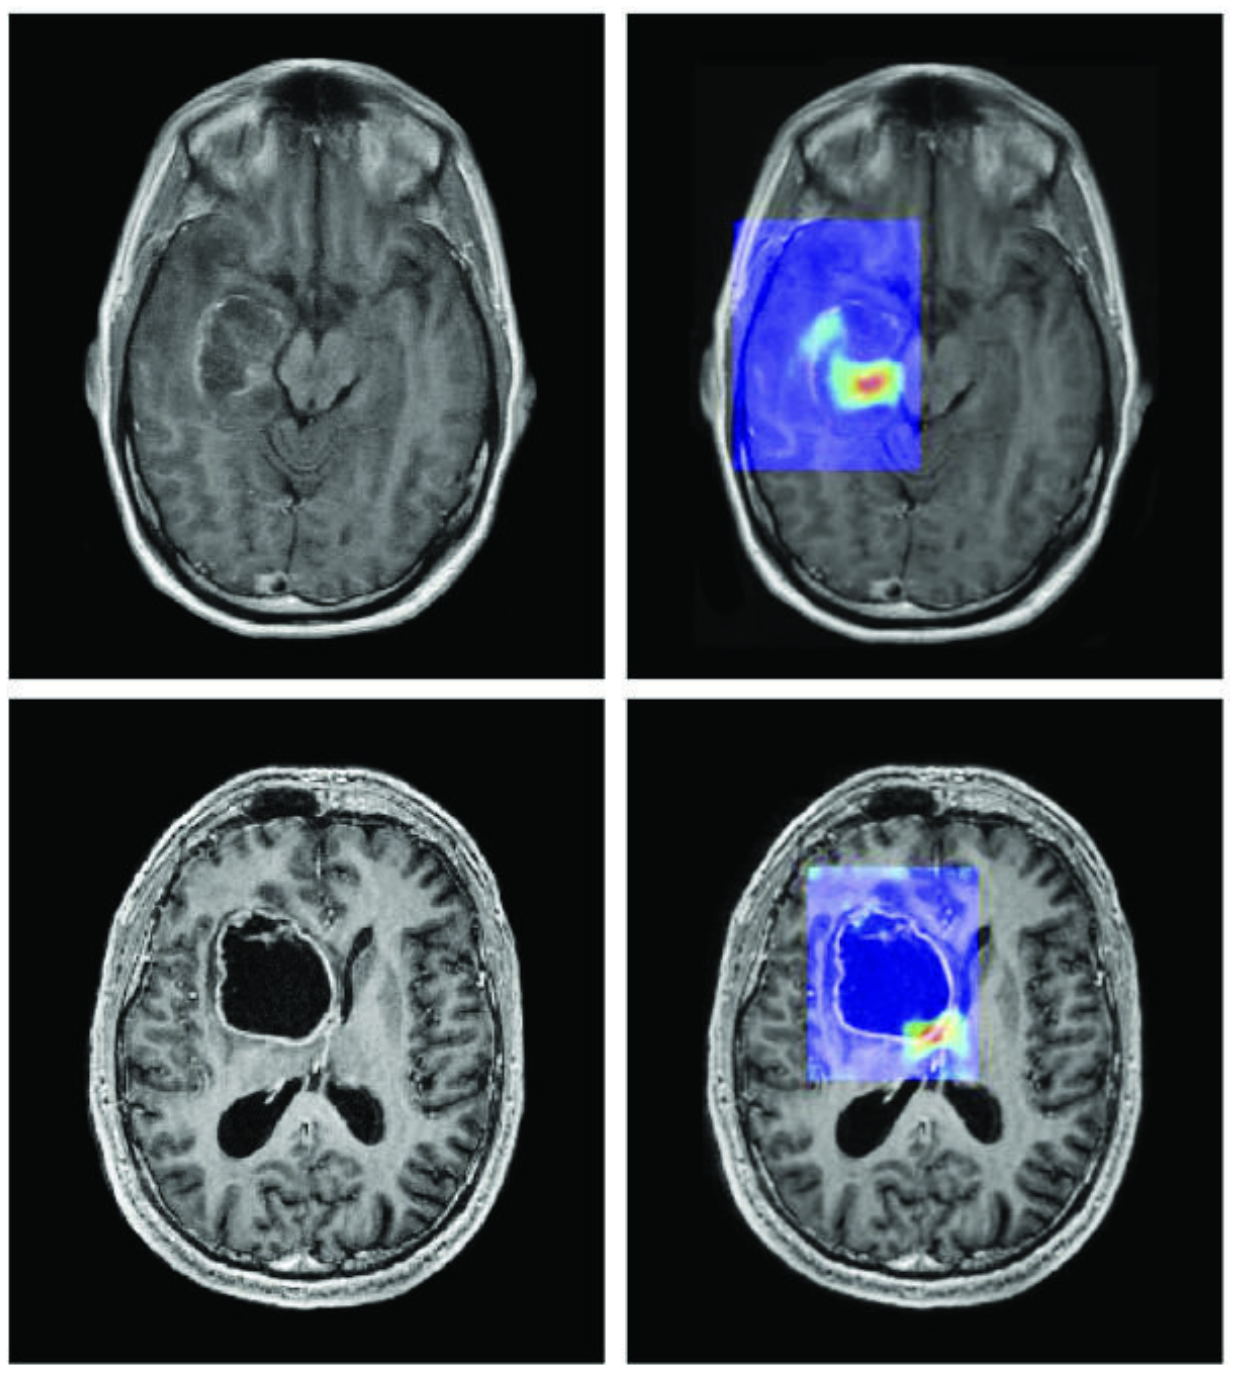

Imagen extraída de: CA Cancer J Clin marzo/abril 2019. DOI: 10.3322/caac.21552. Licencia: CC BY 4.0.

Tres situaciones concretas ilustran ya esta coexistencia eficaz entre el humano y la IA. En medicina, sistemas de IA analizan miles de radiografías en cuestión de segundos para detectar signos precoces de cáncer [1]; pero es el médico quien interpreta el contexto clínico del paciente, establece el diálogo con él y decide el protocolo de tratamiento adecuado: la IA acelera el diagnóstico, pero es el humano quien asume la responsabilidad y el sentido. En la industria, los fabricantes de automóviles utilizan la IA para controlar la calidad en las líneas de producción [2], identificando defectos invisibles a simple vista; pero son los ingenieros los que diseñan los procesos, ajustan los umbrales de tolerancia y toman decisiones cuando un problema se sale del marco previsto por el algoritmo. Finalmente, en la investigación científica, la IA desarrollada por DeepMind ha permitido predecir la estructura tridimensional de más de doscientos millones de proteínas [3], un trabajo que habría llevado siglos si los investigadores hubieran trabajado solos; pero son los biólogos y los químicos los que formulan las hipótesis, diseñan los experimentos y transforman estas predicciones en tratamientos o materiales nuevos. En cada uno de estos casos, la lección es la misma: la IA no sustituye al humano, sino que multiplica su capacidad de acción.